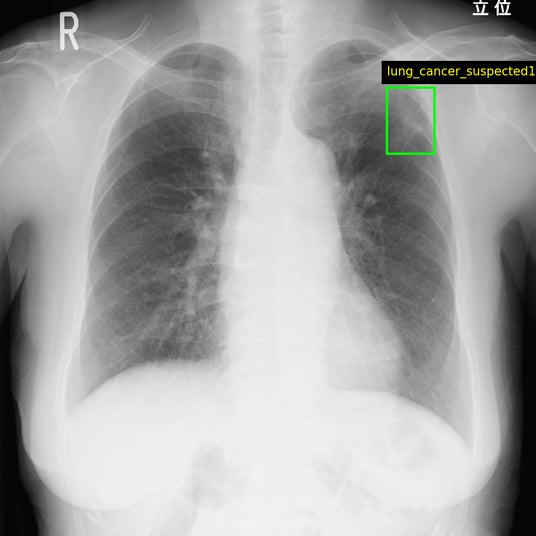

Callisto DataHub 2周年を記念し、専門医が作成した病変BBox付きの肺がん疑いX線データセット 50症例と、病変セグメンテーション付きの前立腺がんMRIデータセット(PI-RADS 4・5) 50症例を無料配布しています。前立腺がんMRIデータセットには、T1w, T2w, DWI, ADC, (あれば)DCEが含まれます。いずれも日本の医療施設由来で、所見文付き・商用利用可能なデータセットです。

肺がん疑いX線データセット